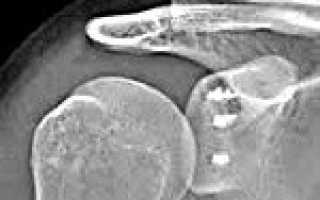

Установлено, что развитию данной патологии способствует повреждение суставной губы (повреждение Банкарта). Суставная губа является волокнисто-хрящевым образованием, которое прикрепляется к суставной впадине лопатки, делая вогнутую поверхность плечевого сустава более глубокой и препятствуя разобщению головки плеча и впадины лопатки при интенсивных движениях. Кроме того, у больных с привычными вывихами часто наблюдаются заднебоковые дефекты головки плечевой кости, обусловленные компрессионным переломом, не выявленным во время первичного травматического вывиха.

Операция Банкарта может проводиться как классическим способом (через обычный разрез), так и с использованием артроскопического оборудования. В последнем случае в области сустава делают два небольших разреза длиной 1-2 тд , через разрезы вводят артроскоп и манипуляторы, после чего под контролем зрения выполняют все необходимые элементы хирургического вмешательства. Использование артроскопической техники позволяет существенно снизить травматичность операции, минимизировать риск развития осложнений и сократить срок реабилитации пациента. В настоящее время эта методика становится золотым стандартом при лечении привычных вывихов плеча.